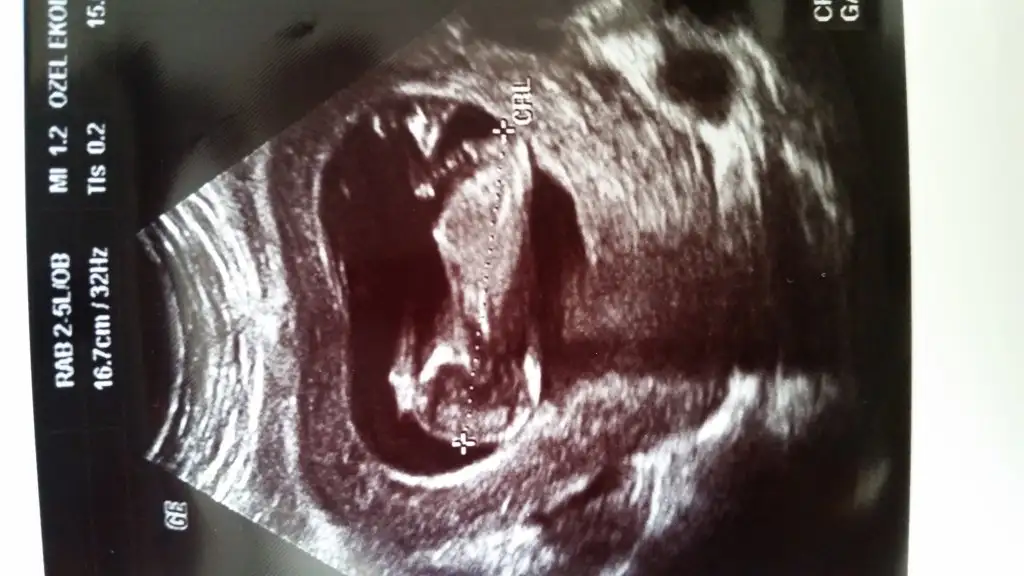

Mervecim bebişin hayırlı olsun,sağlıkla kucağına alırsın inşallah.bir kız haberi de benden,benim de ikinci bebeğim,ilki kızdı bu da kızmış.hayırlısı,sağlıklı sıhhatli olsunlar da.dün dr gittim 14+2de ikili tarama sonucum gelmiş,ona bakarken bebişin de %99 kız olduğunu söyledi,bende gördüm.ilk kızım gibiydi.sen nuba göre kız demiştin,bir erkek,bir kız yorumu olmuştu.Kızçem geliyor.İnşallah herkes en kısa zamanda öğrenir